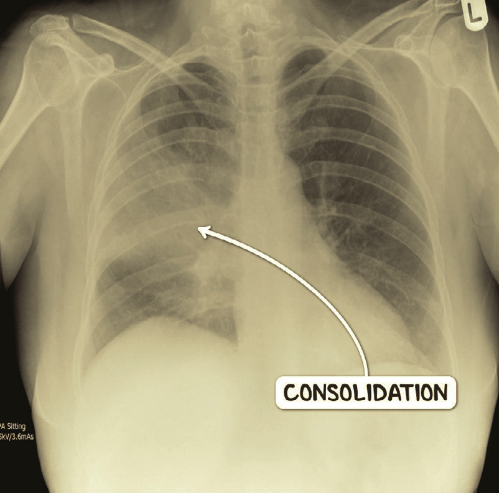

What will a CXR show in Pneumonia? (2 things)